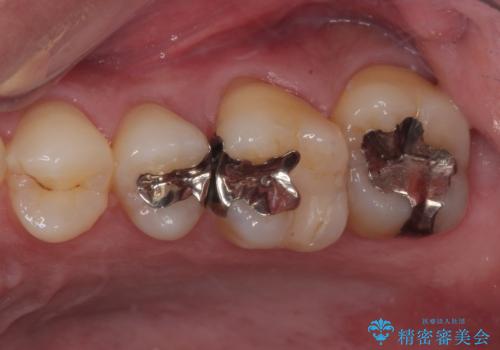

- 左下欠損部のインプラント治療を希望して来院された患者様です。

左下の欠損部を長期間欠損を放置していたことで、咬み合う上の奥歯が動いてしまっている状態でした。

インプラント部は埋入とともに仮歯を装着し、同時に上顎奥歯の部分矯正を開始することとしました。

理想的な咬み合わせに改善した上で、インプラント補綴治療を行うこととしました。